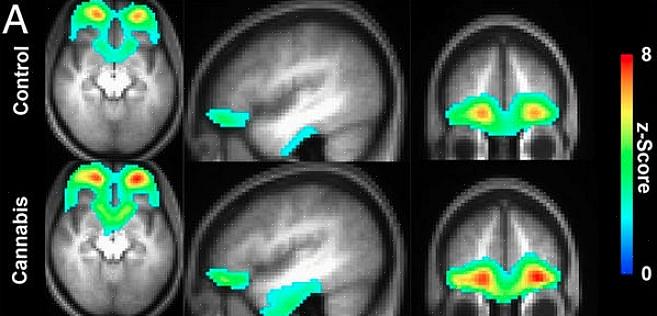

החוקרים השתמשו גם בהדמיה עצבית כדי לחקור עוד יותר את ההשפעות של קנאביס. הם ראו שחומר זה שמקורו בקנאביס מושפע באזורים במוח האחראים על למידה, אחסון וגישה לזיכרון.

חשיפה כרונית לחומר זה משפיעה עוד יותר על המוח. זה משנה את התקשורת בין אזורי המוח המניעים למידה וזיכרון. "העבודה שלנו מראה בבירור שלצריכה ממושכת של קנבינואידים, כאשר לא משתמשים בה מסיבות רפואיות, יש השפעה שלילית על תפקוד המוח והזיכרון", הסבירו החוקרים.